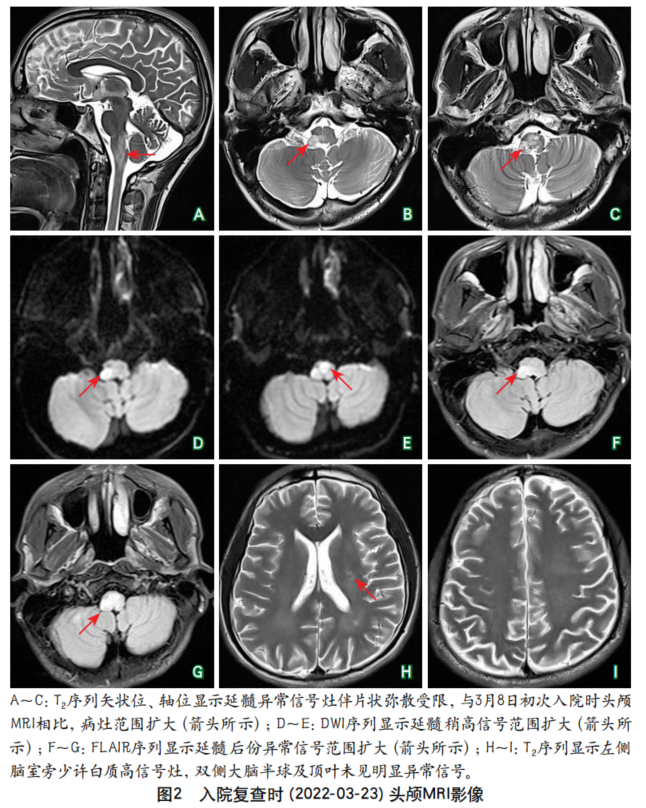

摘要:肥大性下橄榄核变性在临床上较为罕见,其典型临床表现包括腭肌阵挛、共济失调、声音嘶哑和眼部症状,而以四肢阵发性震颤为突出表现的患者则更为罕见,此类患者易被漏诊或误诊。本文报道1例继发于脑干(右侧脑桥和中脑)出血、以四肢阵发性震颤为突出表现的肥大性下橄榄核变性患者,介绍其诊断、治疗及随访情况,并结合相关文献探讨此类患者的临床特点,总结其解剖基础、影像学表现、诊断与治疗要点,以提高临床医师对该病的